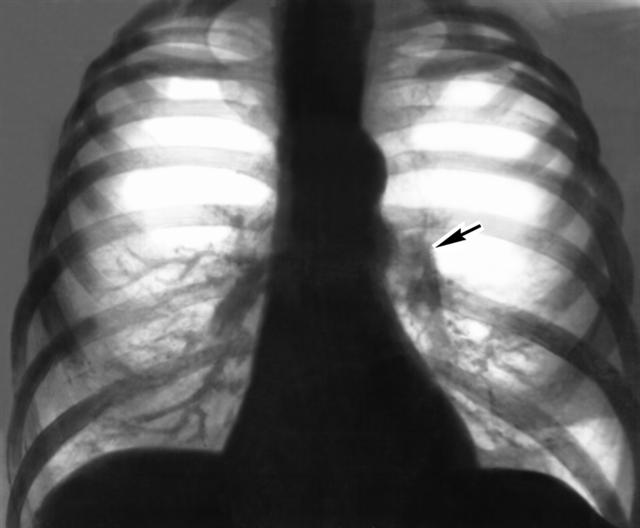

Рис. 4. Рентгенограмма органов грудной полости больного с эмфиземой легких и хроническими легочным сердцем (прямая проекция): сердце имеет относительно небольшие размеры, дуга легочного конуса (указана стрелкой) выбухает, корни расширены за счет крупных ветвей легочных артерий, периферический сосудистый рисунок легких обеднен.